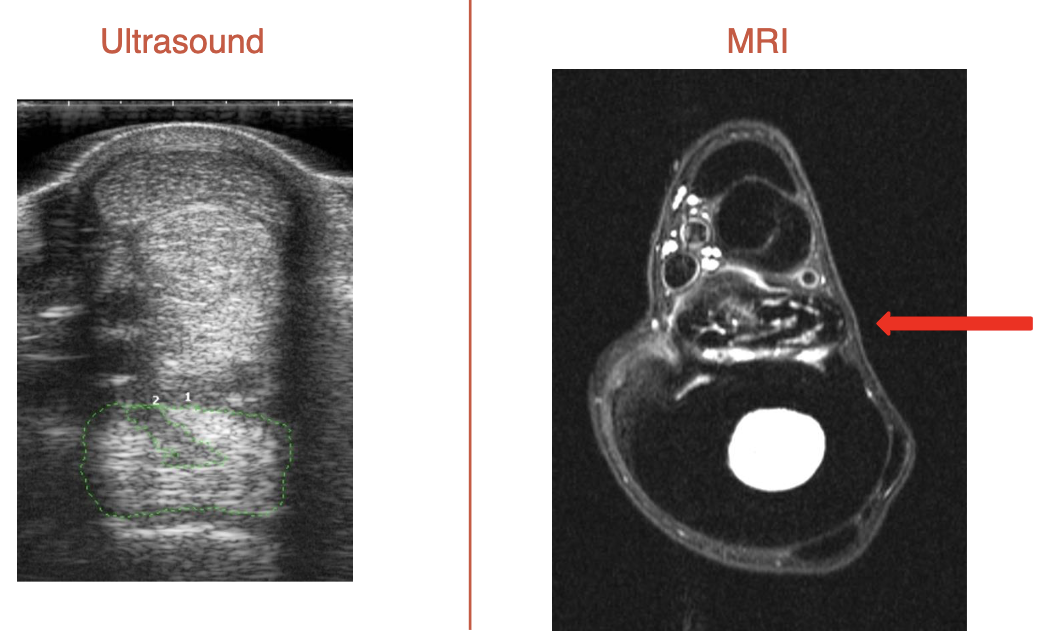

what tendons are torn for these lacerations (L to R)

SDFT only

SDFT & DDFT

SDFT, DDFT, & SL (completely plantigrade)

gastrocnemius lacerations, left to right

normal

gastrocnemeus only (plantigrade stance)

gastroc & SDFT → cannot stand